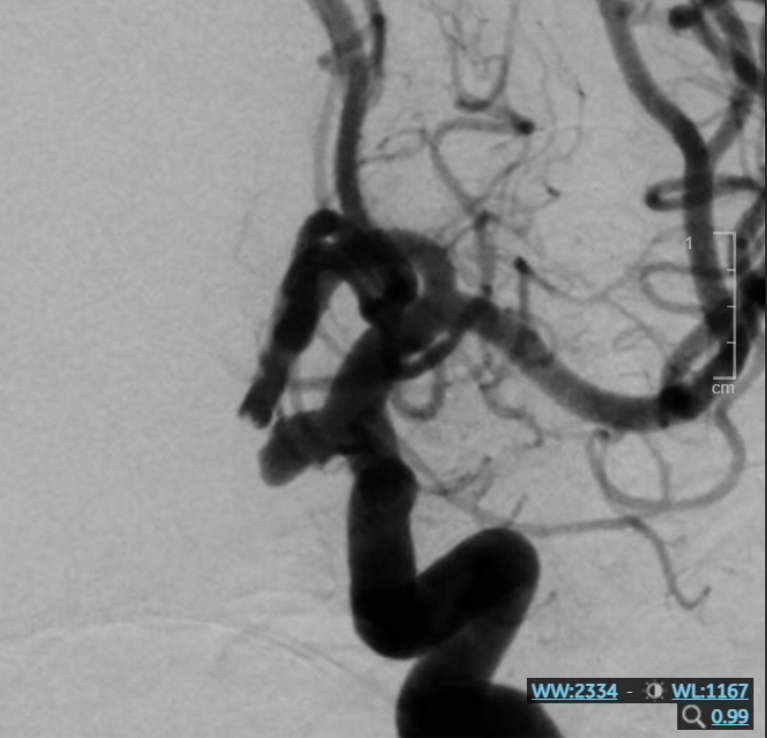

Hình ảnh túi phình mạch máu não trước can thiệp

Bà S.V (52 tuổi, An Giang) đến Bệnh viện Đa khoa Xuyên Á thăm khám do đau lưng kéo dài, gây khó khăn khi đi lại, vận động và sinh hoạt hằng ngày. Trong quá trình khai thác bệnh sử, người bệnh cho biết thêm về tình trạng đau đầu âm ỉ suốt hơn 6 tháng nay của mình. Đây là triệu chứng tưởng chừng không liên quan đến bệnh lý cột sống, nhưng lại khiến bác sĩ nghi ngờ có bất thường tiềm ẩn. Vì vậy, ngoài chỉ định chụp MRI cột sống, bệnh nhân được chỉ định chụp thêm MRI sọ não và CT mạch máu. Kết quả ghi nhận, bà bị thoát vị đĩa đệm tại vị trí L4–L5. Đặc biệt, các bác sĩ đã phát hiện người bệnh có một túi phình động mạch cảnh trong bên trái, kích thước khoảng 7 × 7 mm, tiềm ẩn nguy cơ vỡ cao.

Túi phình của bệnh nhân V. nằm ở vị trí không thể tiếp cận bằng phẫu thuật. Vì thế, sau khi hội chẩn, các bác sĩ thống nhất giải pháp can thiệp nội mạch bằng coil (vòng xoắn kim loại).

BS. Lục Đình Phương – Khoa Sọ Não Cột Sống 2 Bệnh viện Đa khoa Xuyên Á cho biết: “Ca can thiệp này tương đối phức tạp. Túi phình của bệnh nhân có kích thước tương đối lớn, cổ túi phình khá rộng, lại nằm ở góc khuất – góc đảo ngược của dòng chảy mạch máu, gây khó khăn trong việc chọn lọc đưa ống thông vào và đặt coil can thiệp chính xác. Dù vậy, với kinh nghiệm và kỹ năng chuyên môn, ekip bác sĩ đã can thiệp thành công, loại bỏ hoàn toàn túi phình, không để lại biến chứng thần kinh.”